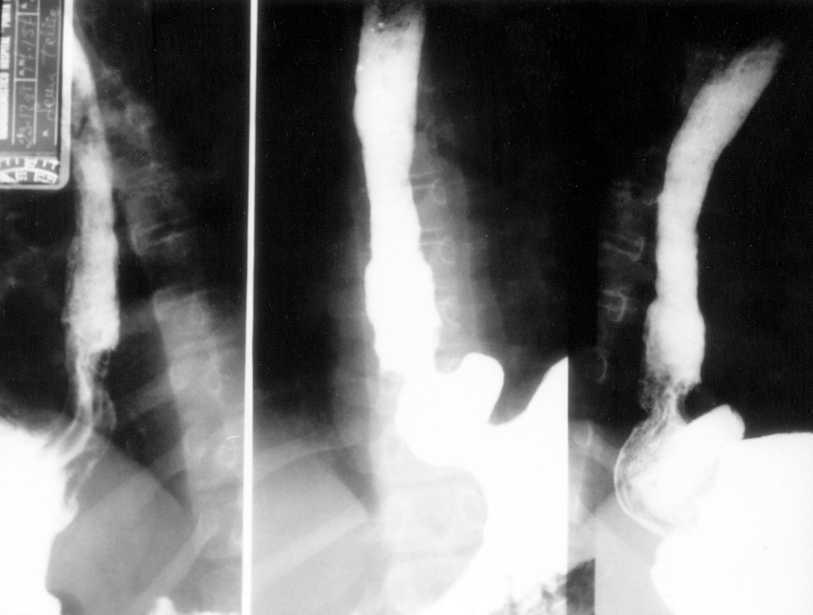

Niña de 6 años enviada para estudio por sospecha de fibrosis quística no refiriéndose antecedentes familiares, gestacionales o perinatales de interés. Desde las primeras semanas de vida había presentado vómitos alimenticio-mucosos y procesos catarrales recurrentes. Al año de edad era evidente el hipocratismo digital. Desde entonces los vómitos fueron atenuándose hasta "desaparecer", siendo sustituidos por episodios de tos acompañados de la emisión de secreciones mucosas de aspecto herrumbroso surcadas, ocasionalmente, por estrías sanguinolentas. A los síntomas citados se añaden, sólo en el mes precedente a la consulta, dolor epigástrico y pirosis. Examen físico. Excelente estado general con manifiesta obesidad (percentiles de peso y talla > 97), discreta palidez cutaneomucosa, dedos hipocráticos con un cociente entre la altura de la falange distal del dedo medio a nivel de la base ungueal y la altura interfalángica distal (AFD/AIF) de 1,25 (normal ≤ 1) (fig. 1), ausencia de alteraciones osteoarticulares y normalidad de la auscultación cardiopulmonar y de la inspección rinofaríngea. Exámenes complementarios: hemoglobina 8,2 g/dl con hipocromía y microcitosis; sideremia 15 μg/dl, ferritina 7 ng/l; recuento plaquetario, curva de distribución del volumen de las plaquetas y niveles del factor Von Willebrand, normales; proteínas totales 5,1 g/dl, albúmina 55 %; hemorragias ocultas en heces positivo en distintas ocasiones; test del sudor repetidamente negativo; parámetros de función pancreática y respiratoria normales; radiografía y tomografía computarizada de tórax, normales; radiografía de la mano, articulaciones mayores y huesos largos, sin artritis ni periostitis; esofagograma: severo RGE asociado a hernia hiatal (fig. 2); esofagoscopia: cardias permanentemente abierto y signos de intensa esofagitis confirmada en el estudio histológico. Los padres rechazaron la realización de pH-metría esofágica y de investigaciones radioisotópicas para detectar la sospechada enteropatía pierde proteínas y a tal efecto se consideró improcedente la realización de un aclaramiento fecal a 1-antitripsina dada la existencia de una hemorragia digestiva en actividad.

Figura 2. Severo reflujo gastroesofágico asociado a hernia hiatal.